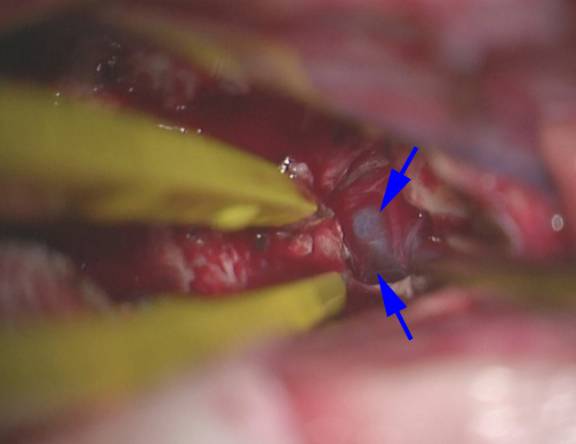

图14. 肿瘤切除后,大脑内静脉(蓝色箭头)可见于瘤腔后方、穹窿开叉处。